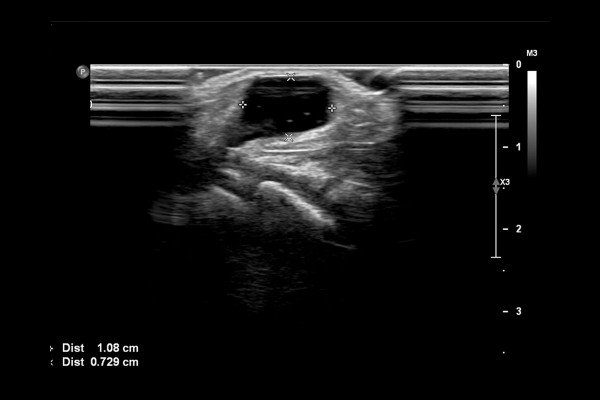

결절종 확인을 위해 초음파 검사를 시행하였고, 초음파 검사 결과, 가로 1cm 깊이 7mm 크기의 물혹이 확인되었습니다.